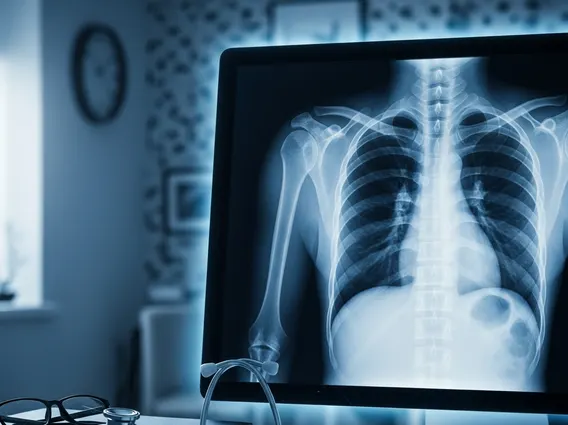

A Chest X Ray serves a broad range of diagnostic purposes, making it one of the most frequently performed imaging tests globally. What is a chest x-ray used for includes diagnosing conditions such as pneumonia, tuberculosis, lung cancer, heart failure, emphysema, and fractured ribs. It can also help monitor the progression of diseases or the effectiveness of treatments.

The chest x-ray procedure information is straightforward and generally takes only a few minutes. Patients will typically be asked to remove any jewelry or metal objects that could interfere with the X-ray image. They will then stand or sit between the X-ray machine and a plate that contains the X-ray film or digital sensor. The radiographer will position the patient, usually requiring them to take a deep breath and hold it for a few seconds to ensure the lungs are fully expanded and the heart is clearly visible. Multiple views, such as a posterior-anterior (PA) view and a lateral view, are often taken to provide a comprehensive assessment of the chest structures. The exposure to radiation is minimal and considered safe for most individuals.